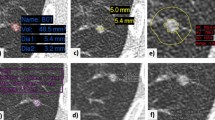

Evaluation of segmentation accuracy

In order to evaluate segmentation accuracy, all packages offered a volume-rendered display that could be turned and a thin-section image in at least one plane that could be scrolled back and forth. Two packages gave the possibility to evaluate the segmentation in other planes as well. The observer visually classified the segmentation accuracy into four categories: (1) ‘excellent’: excellent segmentation, the overlay completely matched the nodule; (2) ‘satisfactory’: although not perfect, the segmented volume is still representative of the nodule. The maximum mismatch between overlay and nodule is visually estimated not to exceed 20% in volume. (3) ‘Poor’: part of the nodule is segmented, but the segmented volume is not representative of the nodule (estimated mismatch >20%). (4) ‘Failure’: No segmentation or the result has no similarity with the lesion. An example of each classification can be found in Fig. 1. In order to exclude the influence of failed segmentations on the reproducibility of a software, nodules were grouped into ‘adequately’ (group 1 and 2) and ‘inadequately’ (group 3 and 4) segmented nodules. Inadequately segmented nodules were excluded from the calculations of inter-examination variability as these segmentations have no value and greatly influence volume measurement reproducibility, making meaningful comparisons impossible.